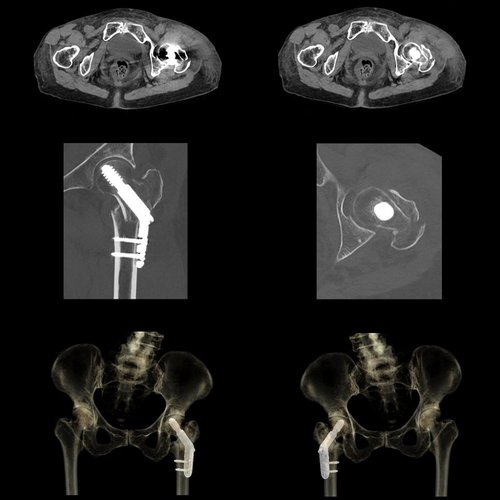

Auch für virtuelle monochromatische Bilder mit 35 keV – 135 keV, die Reduktion von Beam-Hardening-Artefakten, Knochenentfernungen, die Bestimmung der Ordnungszahl, Electron-Density-Bestimmungen und viele andere Anwendungen bietet der Aquilion One PRISM Edition das optimale Gerät.